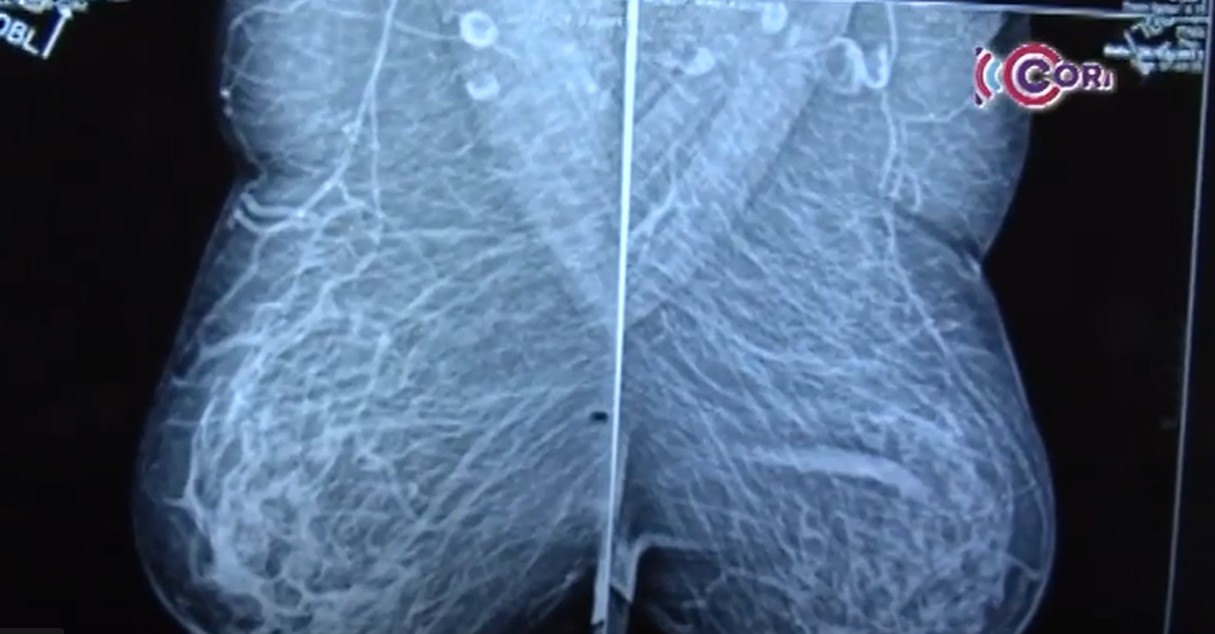

Asiste a la Jornada de Mastografías para prevenir el cáncer de mama

Se realizará el próximo 20 de octubre en la Unidad de Detección y Diagnóstico de Cáncer de Mama, a...

Ofrece IMSS Tlaxcala mil mastografías a mujeres derechohabientes durante el "Mes Rosa"

Con estas acciones impulsa la prevención del cáncer de mama y la promoción de hábitos saludables...

Aumentaron casos de cáncer de mama en mujeres jóvenes de Tlaxcala

Especialistas atribuyen las causas a factores multifactoriales como cambios en los patrones de...